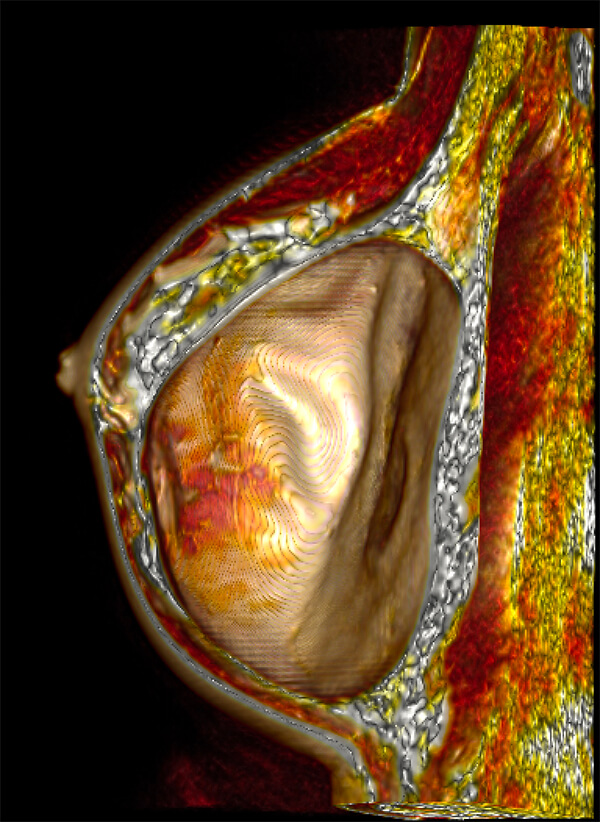

Τρισδιάστατη απεικόνιση ταχείας πρώιμης αιμάτωσης μαστών

- Απεικόνιση με ειδικό πηνίο μαστού (18 channel dedicated breast coil) σε μαγνητικό τομογράφο 3Τesla SIEMENS SKYRA τελευταίας γενιάς

- Εικόνες υψηλής ευκρίνειας (high resolution)